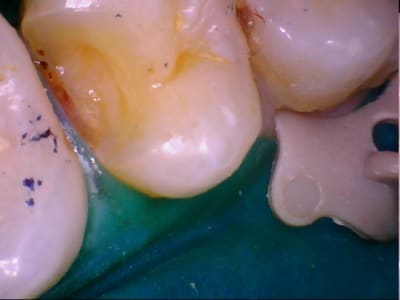

eMax de ce soir.

Collage automordançant G-Cem.

Pour être tout à fait honnête, j'ai collé une base composite, essentiellement pour assurer une stabilité à l'onlay, qui participe aussi à absorber les contraintes.